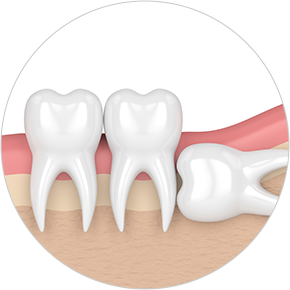

• Horizontally

impacted wisdom tooth

• Angulated

• Vertically